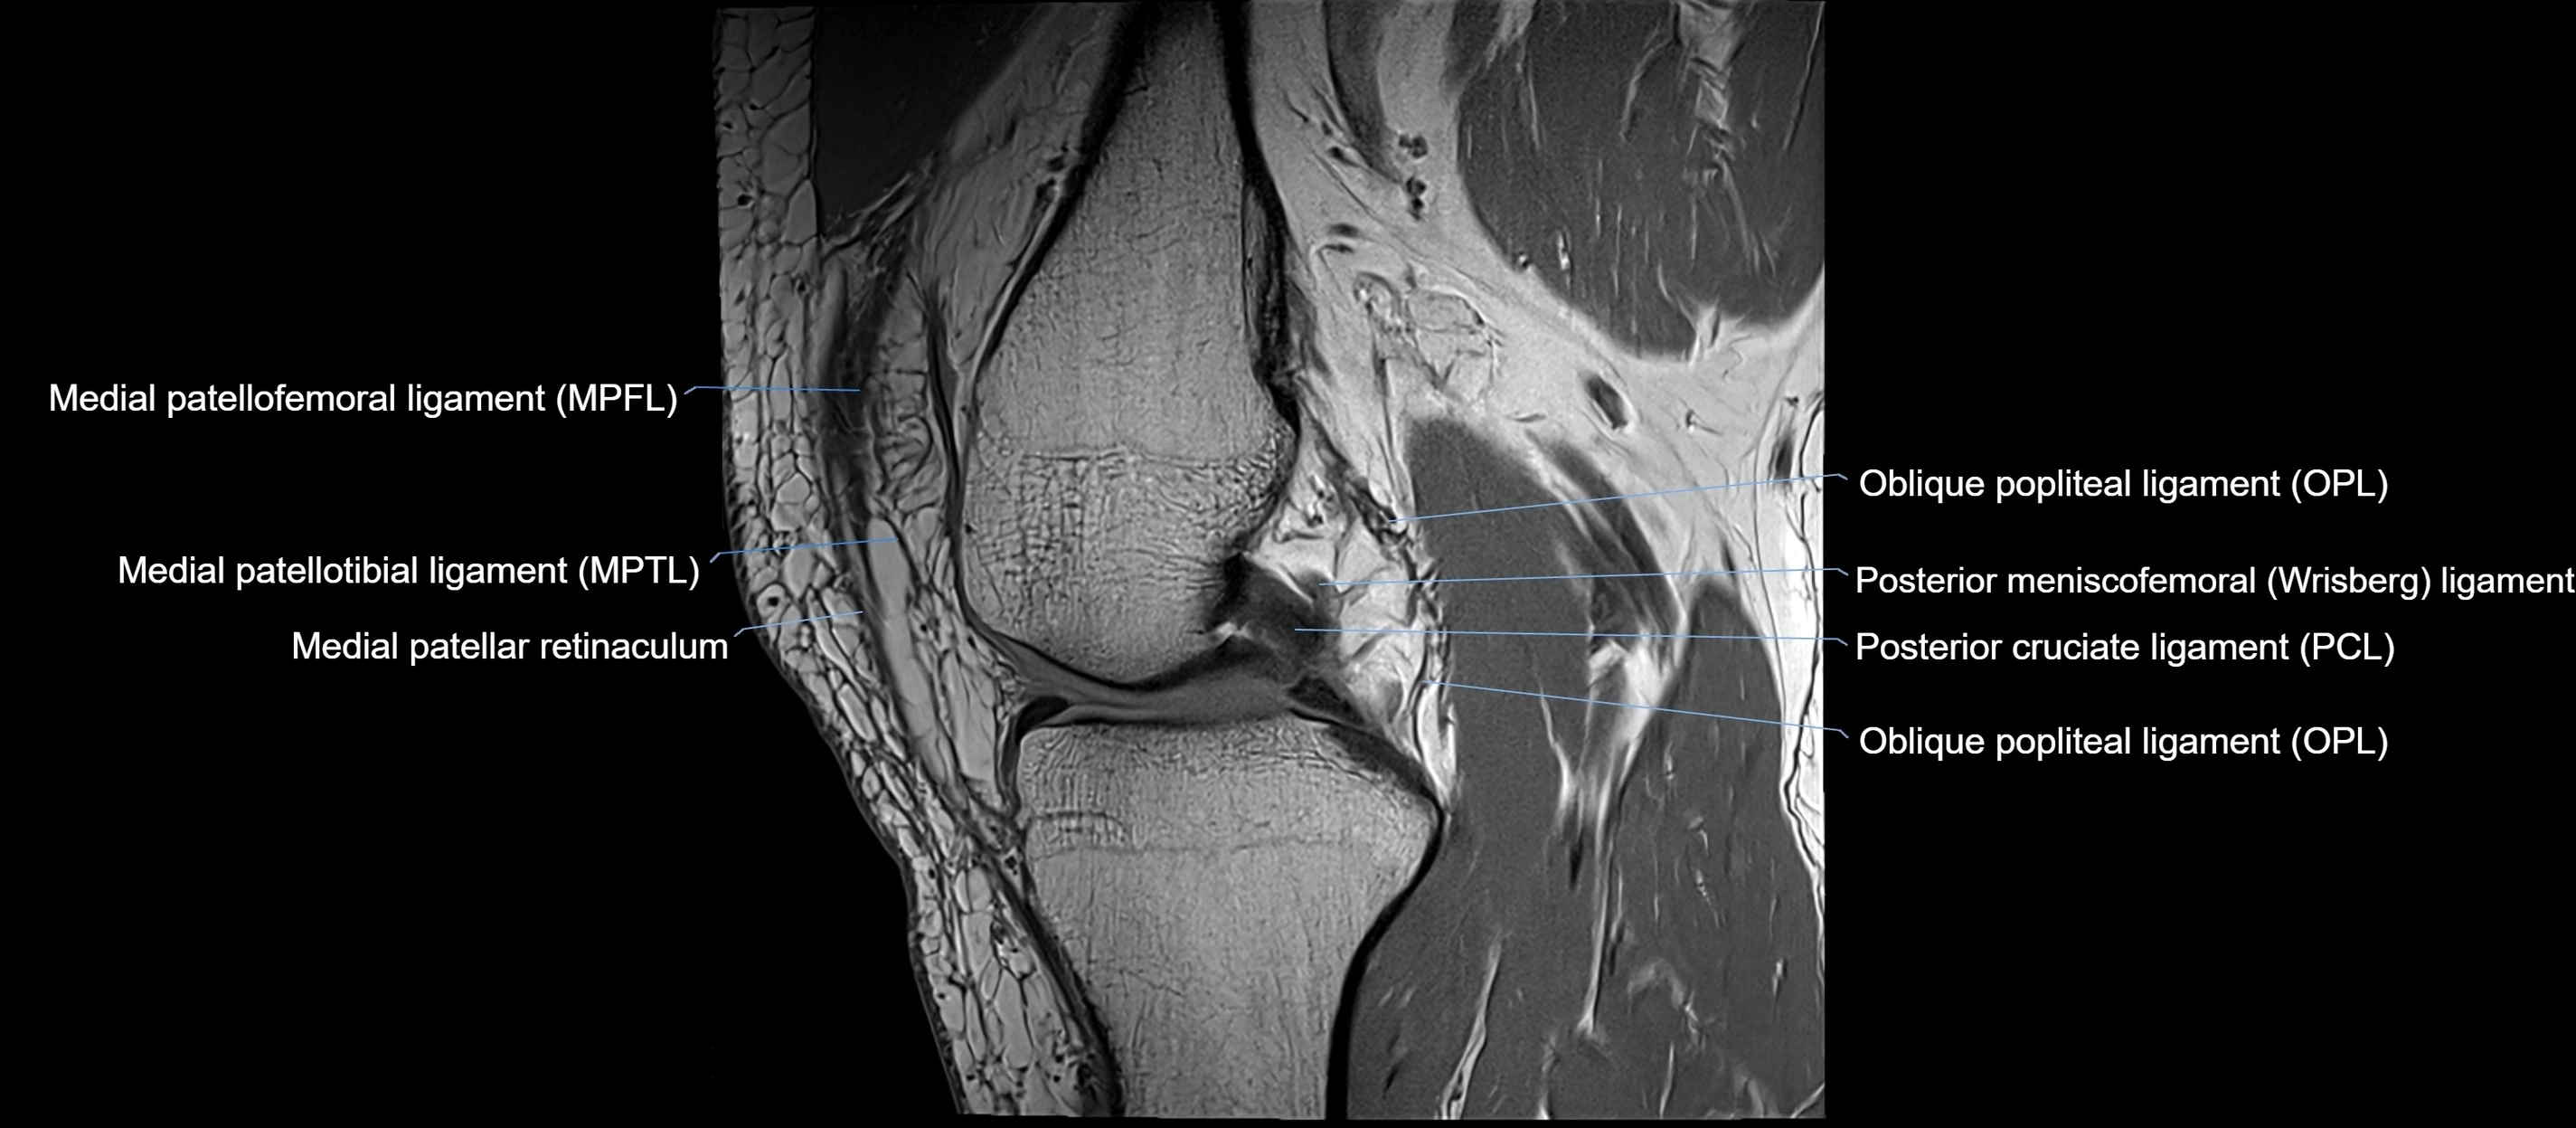

MRI images

image